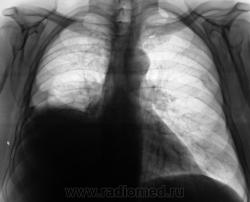

Гемопневмоторакс.

Признаков пневмоторакса по прямой R-грамме не нахожу( в наружном отделе среднего поля справа, явно не воздух т.к.тень значительно плотнее лёгочной ткани), по боковой проекции действительно видна жидкость с горизонтальным уровнем-может быть этот уровень имеет отношение к средостению? Случай непростой, нужна клиника и анамнез.

Как по моему изображению, судить о консолидации справа нельзя. Но слева переломы консолидированные.

Спасибо, уважаемые коллеги! Но дело в том, что пациент "свежую травму", в течение последнего года отрицает. Пациент, весьма не молодого возраста, ведет "добропорядочный" образ жизни - не пьёт, не дебоширит, не замечен...

По видимому этот пациент отправлен в онкологию?не нравиться тень в глубоких отделах S 6,и следствие -жидкость.

Да, Вы правы коллега, пациент направлен в онкологию - ООД.